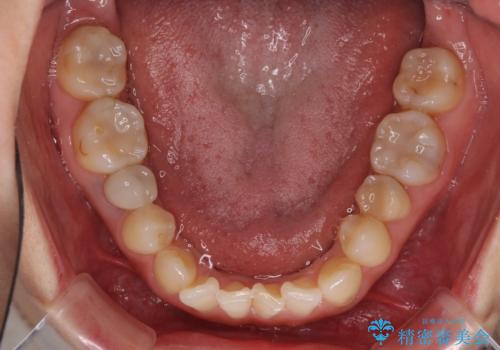

前歯のクロスバイトと治療が必要なむし歯 矯正とセラミックの総合歯科治療

前歯は根管治療が必要であったため、まずは根管治療を行いましたが、痛みが引いた後、矯正治療や前々から治療が必要と言われてきた歯を治療したいとのことでした。

前歯のクロスバイトはインビザラインで改善し、抜歯が必要な部分はインプラントを、その他むし歯が進行している歯はセラミッククラウンによる補綴治療することとしました。

仕事がお忙しく、インビザラインをあまりしっかりと使用できなかったようで、何とか長い期間をかけて歯列を整えることができました。

磨きにくく、何度もむし歯治療を繰り返していた前歯をスッキリと整えることができました。